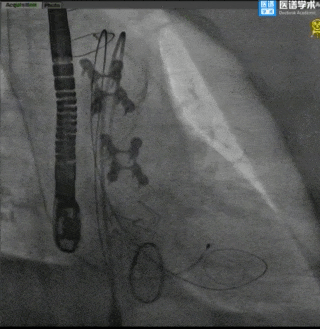

手术过程

主动脉根部造影

球囊预扩

TaurusElite®顺利过弓

TaurusElite®首次释放

TaurusElite®首次回收

TaurusElite®二次释放

TaurusElite®二次回收

TaurusElite®最终释放形态

术后评估

主动脉瓣术后平均压差7mmHg,无瓣周漏。